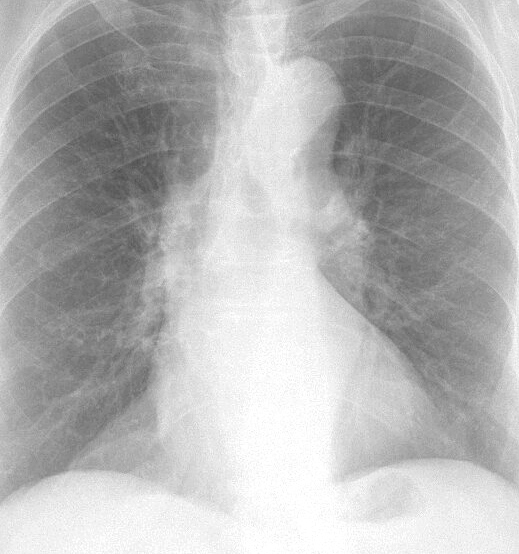

Gallery Mediastinum Fat Pad Fat Pad

Fat Pad